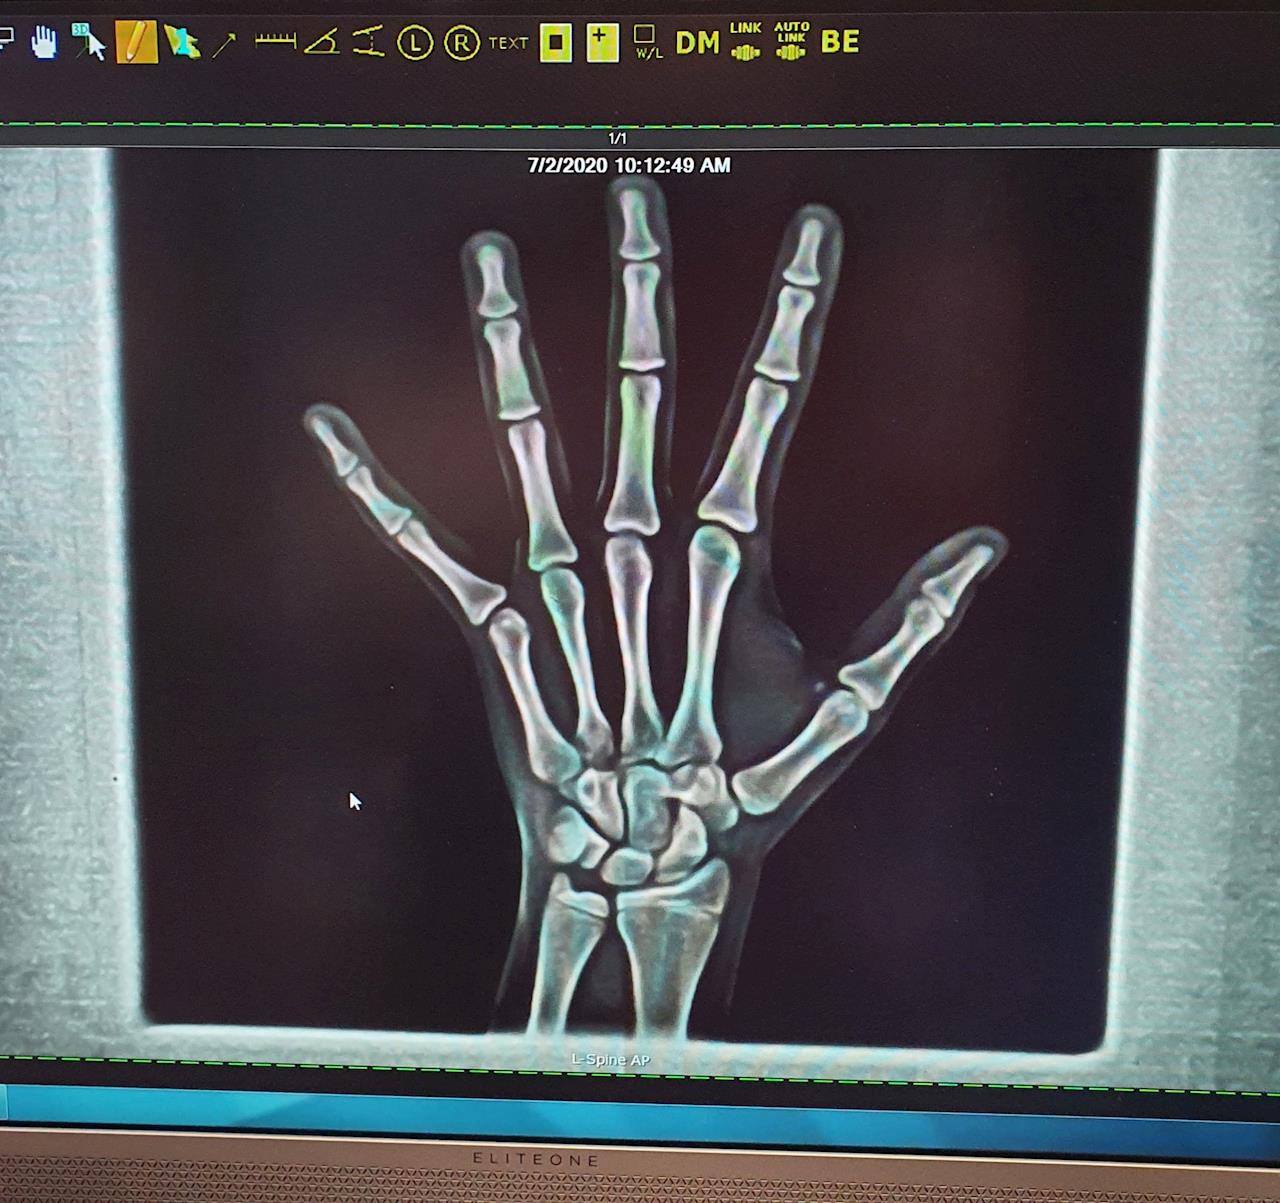

An x-ray of her hand on last visit still shows quite alot of growing to do yet with the growth plates. This is good, she still has time to adjust.